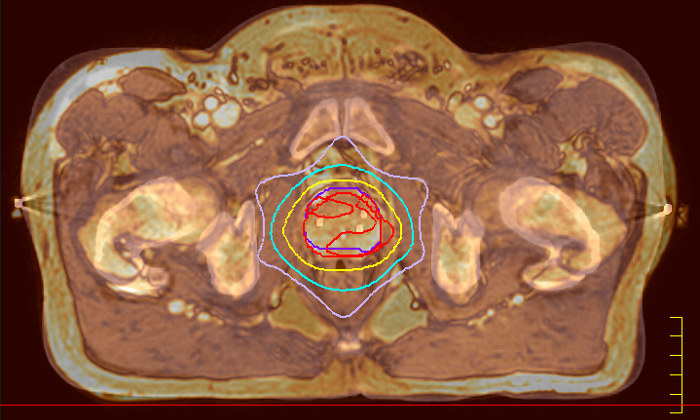

MRI and radiotherapy treatment at the same time

A fully integrated Elekta linear accelerator and 1.5T Philips MRI system usher in the clinical era of high field MR-guided radiotherapy.MR-only simulation in prostate cancer radiotherapy